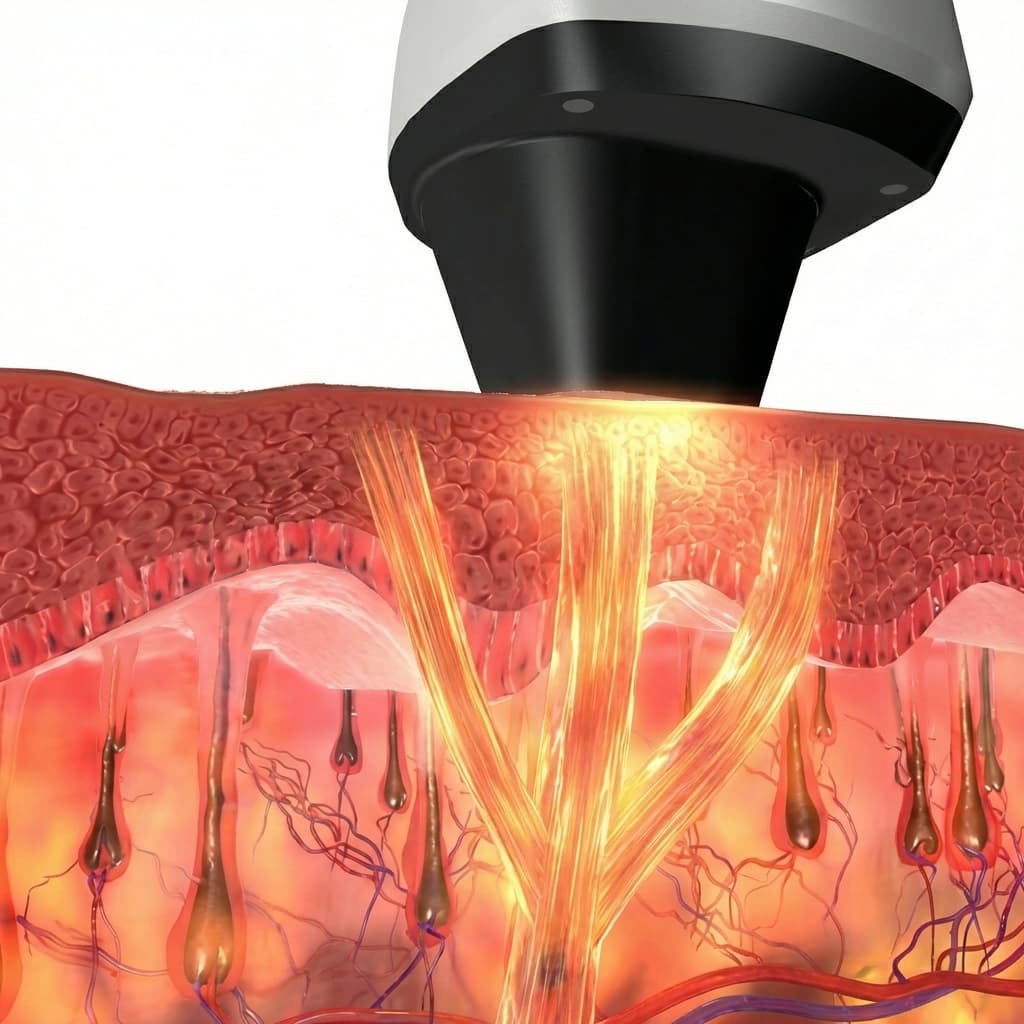

Technology, Principle, Core

Core Technology

Core technology and principles

Equipment/Laser

We provide effective and safe treatments using verified cutting-edge medical equipment and lasers.